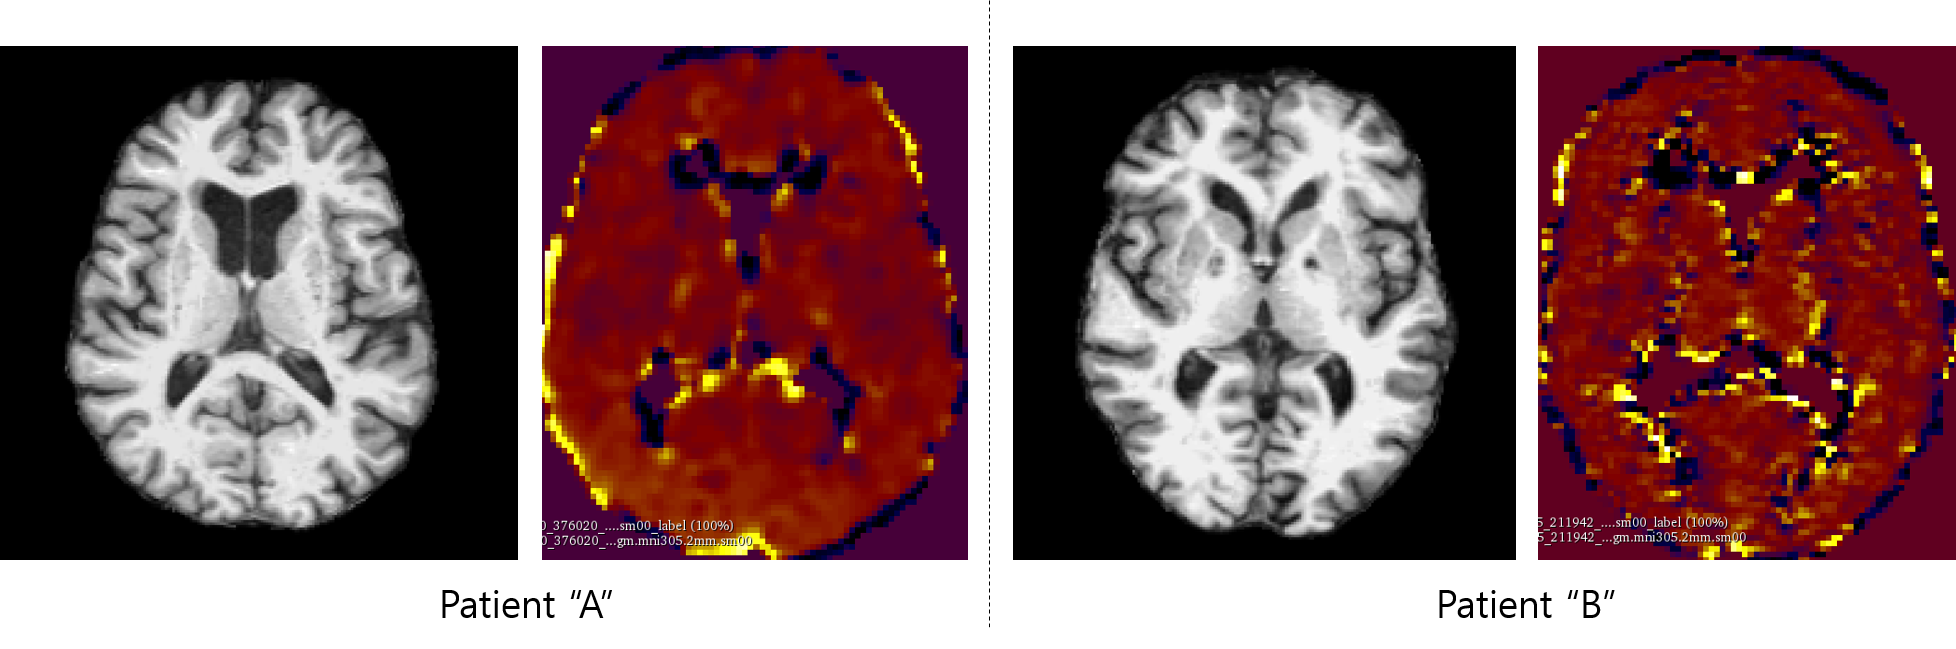

Refer to caption

Figure 1: Examples of T1-weighted MRI and PET images of same patient. T1 images are in 256×256×256256256256256\times 256\times 256 size and PET are N×93×76×76𝑁937676N\times 93\times 76\times 76 size where N is the number of time-points PET is taken. It is challenging to register MRI and PET images.

In this paper, we explore the question of synthesizing PET images from existing MR images. This is a challenging task by nature, because we are expecting to see radioactivity over time from MRI that does not have any. Unlike semantic segmentation where the “paired” [5, 17] images (e.g., images and sketches, label maps) mostly have perfect matching, MRI and PET images look quite different even though imaging the same object. An example of MRI and corresponding PET is shown in Figure 1. It is also a difficult task from a deep learning perspective, since PET imaging can result in images whose intensities range between -100 to 1000 or more, in floating point values, as shown in Figure 2.

5.2 Visual Examples of Generated PET Images

Examples of AV45-PET images generated by GANBERT and pix2pix are compared with the original PET image in Figure 1. GANBERT manages to generate close to the original AV45-PET image while pix2pix fails to generate a reasonable image. Some more examples of AV1451- and FDG- PET images generated by GANBERT are compared with the original PET images in Figure 2. Overall, images to close to the original PET images are generated by GANBERT in all three PET imaging techniques tested. The image quality of the center of the brain region is not as good as the other region, and it is suspected due to (1) differences in MRI and PET images, and (2) lack of training data.